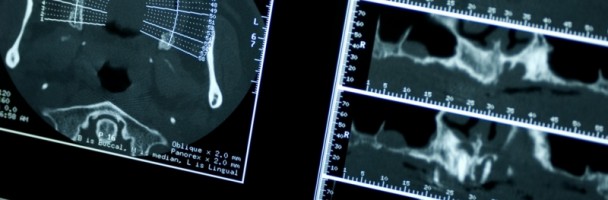

Per una valutazione ancora più accurata della struttura condilo-mandibolare disponiamo della TC Cone Beam 3D per lo studio morfologico delle ATM che attraverso ricostruzioni tridimensionali permette di studiare le modifiche ossee del condilo (appiattimento, erosione, sclerosi, osteofitosi,riassorbimento), lo spazio interarticolare (normale, aumentato, ridotto, contatto osseo tra condilo e fossa mandibolare) e le modifiche ossee della fossa mandibolare.

La Tomografia computerizzata a fascio conico è una tecnologia che permette l’acquisizione di immagini radiografiche in 3D di una parte o di tutto il cranio del paziente, con l’utilizzo di dosi di radiazioni minori alle dosi utilizzate nei tomografi convenzionali.

La Tc 3d Cone Beam presenta numerosi vantaggi rispetto ad altre modalità di esami  grazie all’esattezza , alla velocità nell’acquisizione delle immagini e alla sicurezza nei confronti del Paziente.

La Tc 3D Cone Beam puo’ essere utilizzata nella pratica clinica attualmente per la diagnostica e il piano di trattamento in diverse branche della medicina quali Chirurgia, Implantologia e Patologia orale, permettendo di identificare i punti anatomici come appaiono nel maxillo e nella mandibola.

Permette di ridurre al minimo le dosi di radiazione e il tempo di esposizione oscilla tra i 15/20 secondi.

La riduzione della dose effettiva di radiazioni ricevute dal paziente è quasi il 90% inferiore rispetto ad una Tc convenzionale. In più permette di adeguare le dosi di radiazioni in base al paziente, in modo che un bambino ne riceva il 50% in meno rispetto ad un adulto.

Newtom 5G è caratterizzato da un lettino motorizzato che permette di acquisire le immagini con il paziente comodamente disteso in posizione supina. E’ stato infatti dimostrato che, con una posizione rilassata senza elementi di fissaggio o costrizione della testa, il paziente mantiene più facilmente l’immobilità, migliorando la qualità dell’esame.

L’immagine digitale e la ricostruzione 3D permette di realizzare la collocazione virtuale degli impianti e dunque pianificare i trattamenti con maggiore precisione, meno complicazioni e risultati migliori.

L’imaging Cone Beam utilizza invece un fascio a forma conica per acquisire l’intero volume, effettuando un’unica rotazione. Il risultato sarà un’immagine più accurata, che contiene una serie completa di informazioni, ottenuta con un tempo di esposizione ai raggi X considerevolmente inferiore rispetto a una Tac convenzionale.